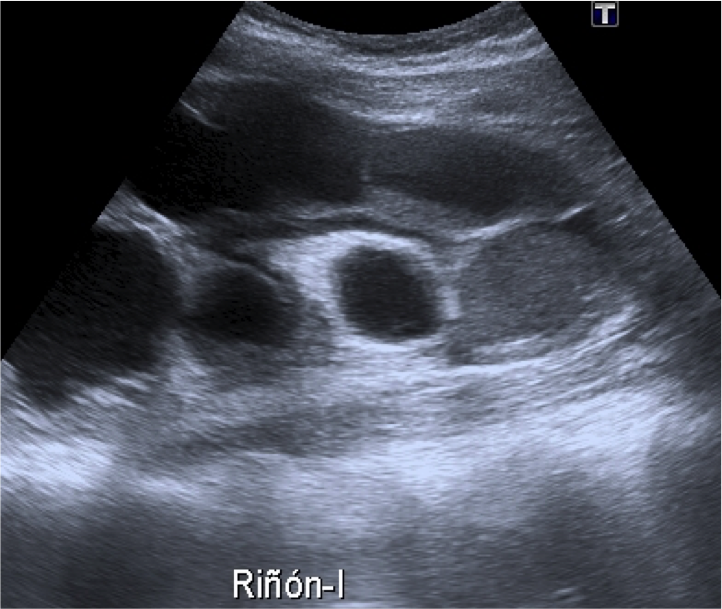

Arriba, se observa un quiste cortical simple con contenido anecogénico.